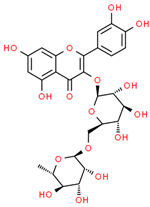

| Sr. No. | Name | PubChem ID | MF | MW | Canonical SMILES | Structure |

|---|---|---|---|---|---|---|

| 1 | Apigenin | 5280443 | C15H10O5 | 270.24 | C1=CC(=CC=C1C2=CC(=O)C3=C(C=C(C=C3O2)O)O)O |  |

| 2 | Caffeic acid | 689043 | C9H8O4 | 180.16 | C1=CC(=C(C=C1C=CC(=O)O)O)O |  |

| 3 | Catechin | 9064 | C15H14O6 | 290.27 | C1C(C(OC2=CC(=CC(=C21)O)O)C3=CC(=C(C=C3)O)O)O |  |

| 4 | Chlorogenic acid | 1794427 | C16H18O9 | 354.31 | C1C(C(C(CC1(C(=O)O)O)OC(=O)C=CC2=CC(=C(C=C2)O)O)O)O |  |

| 5 | Digalacturonic acid | 439694 | C12H18O13 | 370.26 | C1(C(C(OC(C1O)OC2C(C(C(OC2C(=O)O)O)O)O)C(=O)O)O)O |  |

| 6 | Ferullic acid | 445858 | C10H10O4 | 194.18 | COC1=C(C=CC(=C1)C=CC(=O)O)O |  |

| 7 | Gallic acid | 370 | C7H6O5 | 170.12 | C1=C(C=C(C(=C1O)O)O)C(=O)O |  |

| 8 | Iso-quercetin | 10813969 | C21H20O12 | 464.4 | C1=CC(=C(C=C1C2=C(C(=O)C3=C(C=C(C=C3O2)O)O)OC4C(C(C(C(O4)CO)O)O)O)O)O |  |

| 9 | Luteolin | 5280445 | C15H10O6 | 286.24 | C1=CC(=C(C=C1C2=CC(=O)C3=C(C=C(C=C3O2)O)O)O)O |  |

| 10 | Myricetin | 5281672 | C15H10O8 | 318.23 | C1=C(C=C(C(=C1O)O)O)C2=C(C(=O)C3=C(C=C(C=C3O2)O)O)O |  |

| 11 | p-coumaric acid | 637542 | C9H8O3 | 164.16 | C1=CC(=CC=C1C=CC(=O)O)O |  |

| 12 | Protocatechuic acid | 72 | C7H6O4 | 154.12 | C1=CC(=C(C=C1C(=O)O)O)O |  |

| 13 | Quercetin | 5280343 | C15H10O7 | 302.23 | C1=CC(=C(C=C1C2=C(C(=O)C3=C(C=C(C=C3O2)O)O)O)O)O |  |

| 14 | Resorcinol | 5054 | C6H6O2 | 110.11 | C1=CC(=CC(=C1)O)O |  |

| 15 | Rutin | 5280805 | C27H30O16 | 610.5 | CC1C(C(C(C(O1)OCC2C(C(C(C(O2)OC3=C(OC4=CC(=CC(=C4C3=O)O)O)C5=CC(=C(C=C5)O)O)O)O)O)O)O)O |  |

| 16 | β-Carotene | 5280489 | C40H56 | 536.9 | CC1=C(C(CCC1)(C)C)C=CC(=CC=CC(=CC=CC=C(C)C=CC=C(C)C=CC2=C(CCCC2(C)C)C)C)C |  |

| 17 |  | 222284 | C29H50O | 414.7 | CCC(CCC(C)C1CCC2C1(CCC3C2CC=C4C3(CCC(C4)O)C)C)C(C)C |  |